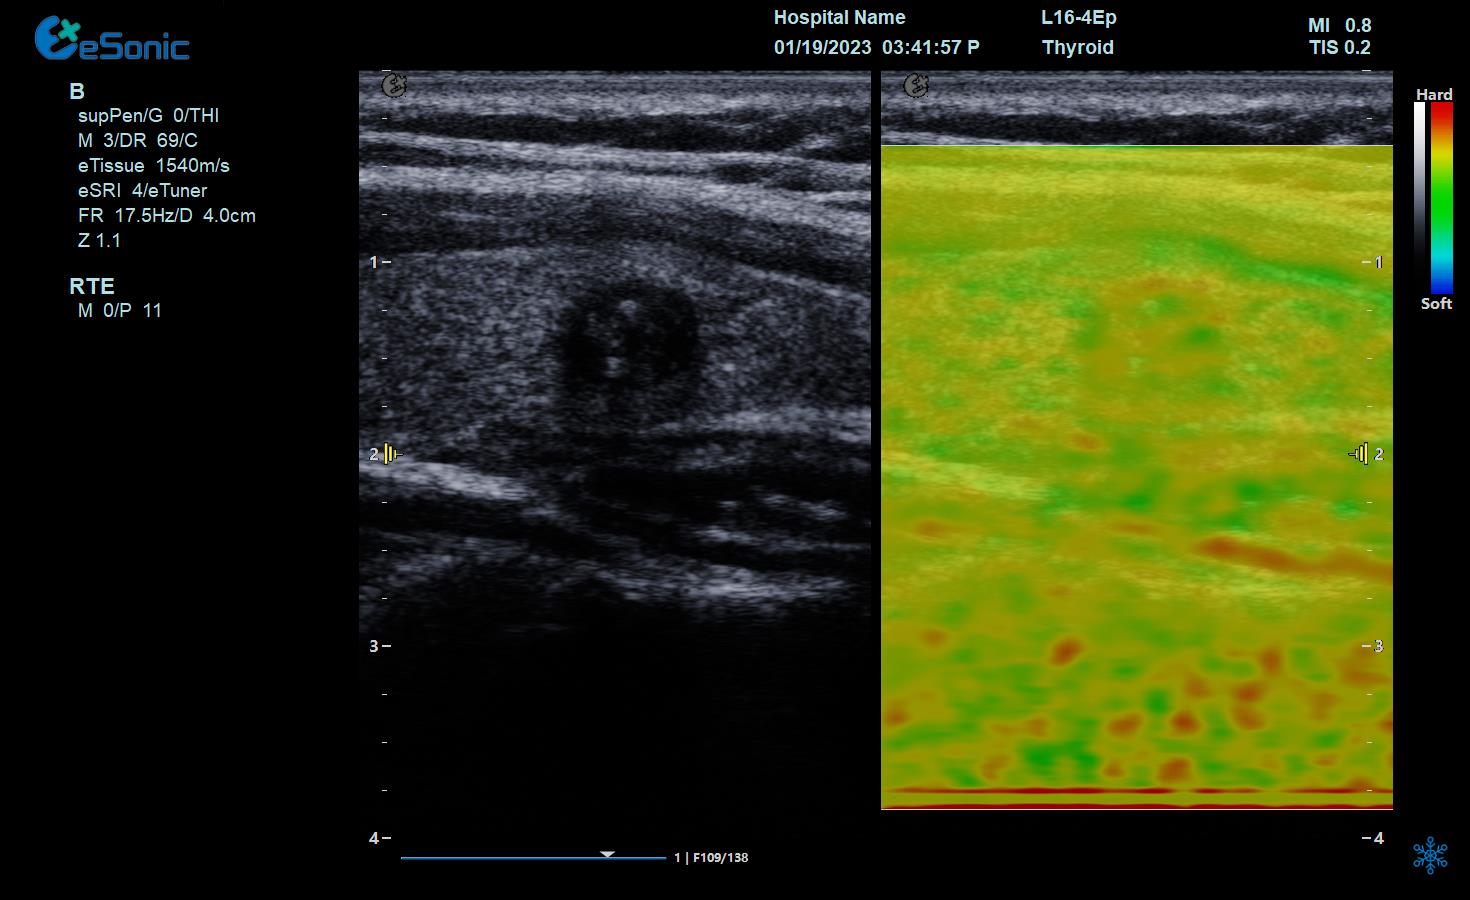

实时弹性成像

智能Map技术